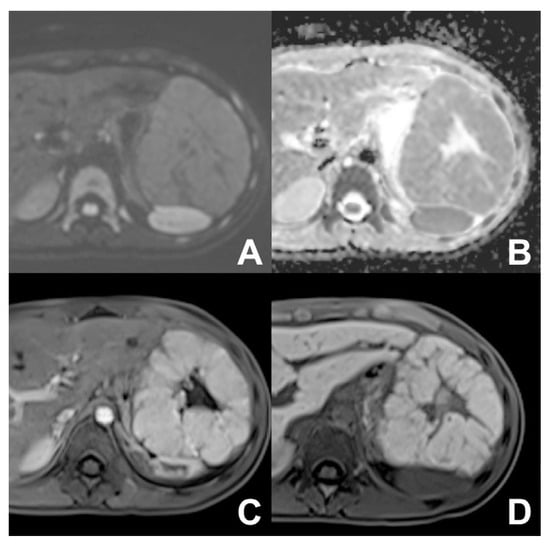

| Follow-up oncological Patient | HASTE T2 | AXIAL | -- | -- | Anatomy and liquids analysis |

| INDICATIONS: MRI is the technique of choice in young patients and pregnant women after a unclear US finding. Moreover, it is useful even after a CT with undefined diagnosis for all patients. It can be alternated to CT in young patients with a long follow-up. | HASTE T2 | CORONAL | -- | -- | Anatomy and liquids analysis |

| DWI b 0–50–400–800 | AXIAL | -- | -- | DWI b50 increases the sensitivity of mets detection | |

| GRE T1 IN/OUT | AXIAL | -- | -- | Steatosis | |

| GRE T1 3D DYNAMIC | AXIAL | PRE-ART 25″-PORTAL 70″-LATE 180″ | YES | HBP increases the sensitivity of metastases detection | |